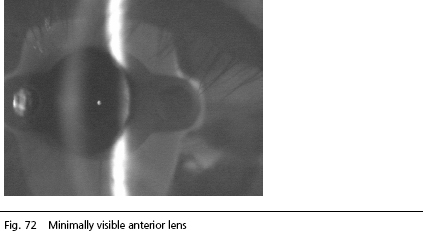

IOLMaster Arizona Note: It will suffice if a relatively small section of the lens is visible. The picture below shows an alignment that permits accurate measurement.

The image is sufficient for the calculation of the anterior chamber depth. (In the photo above, the front side of the IOL Master is visible as a non-disturbing artifact).